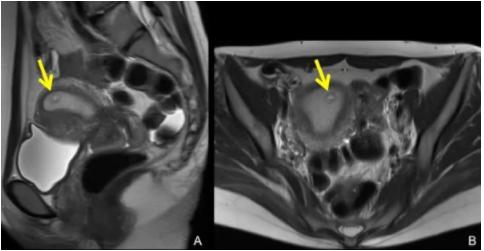

请点击此处孕5周子宫的疤痕(左图)和孕囊(右图)输入图片描述

3、孕6~8周检查胚胎着床位置。头胎剖了的孕妈,在孕40-50天时,到医院做B超检查,确认孕囊没有长在第一次手术的瘢痕上。孕期要注意,如果出现不明原因的腹痛,一定要想到子宫破裂的可能,及时处理。